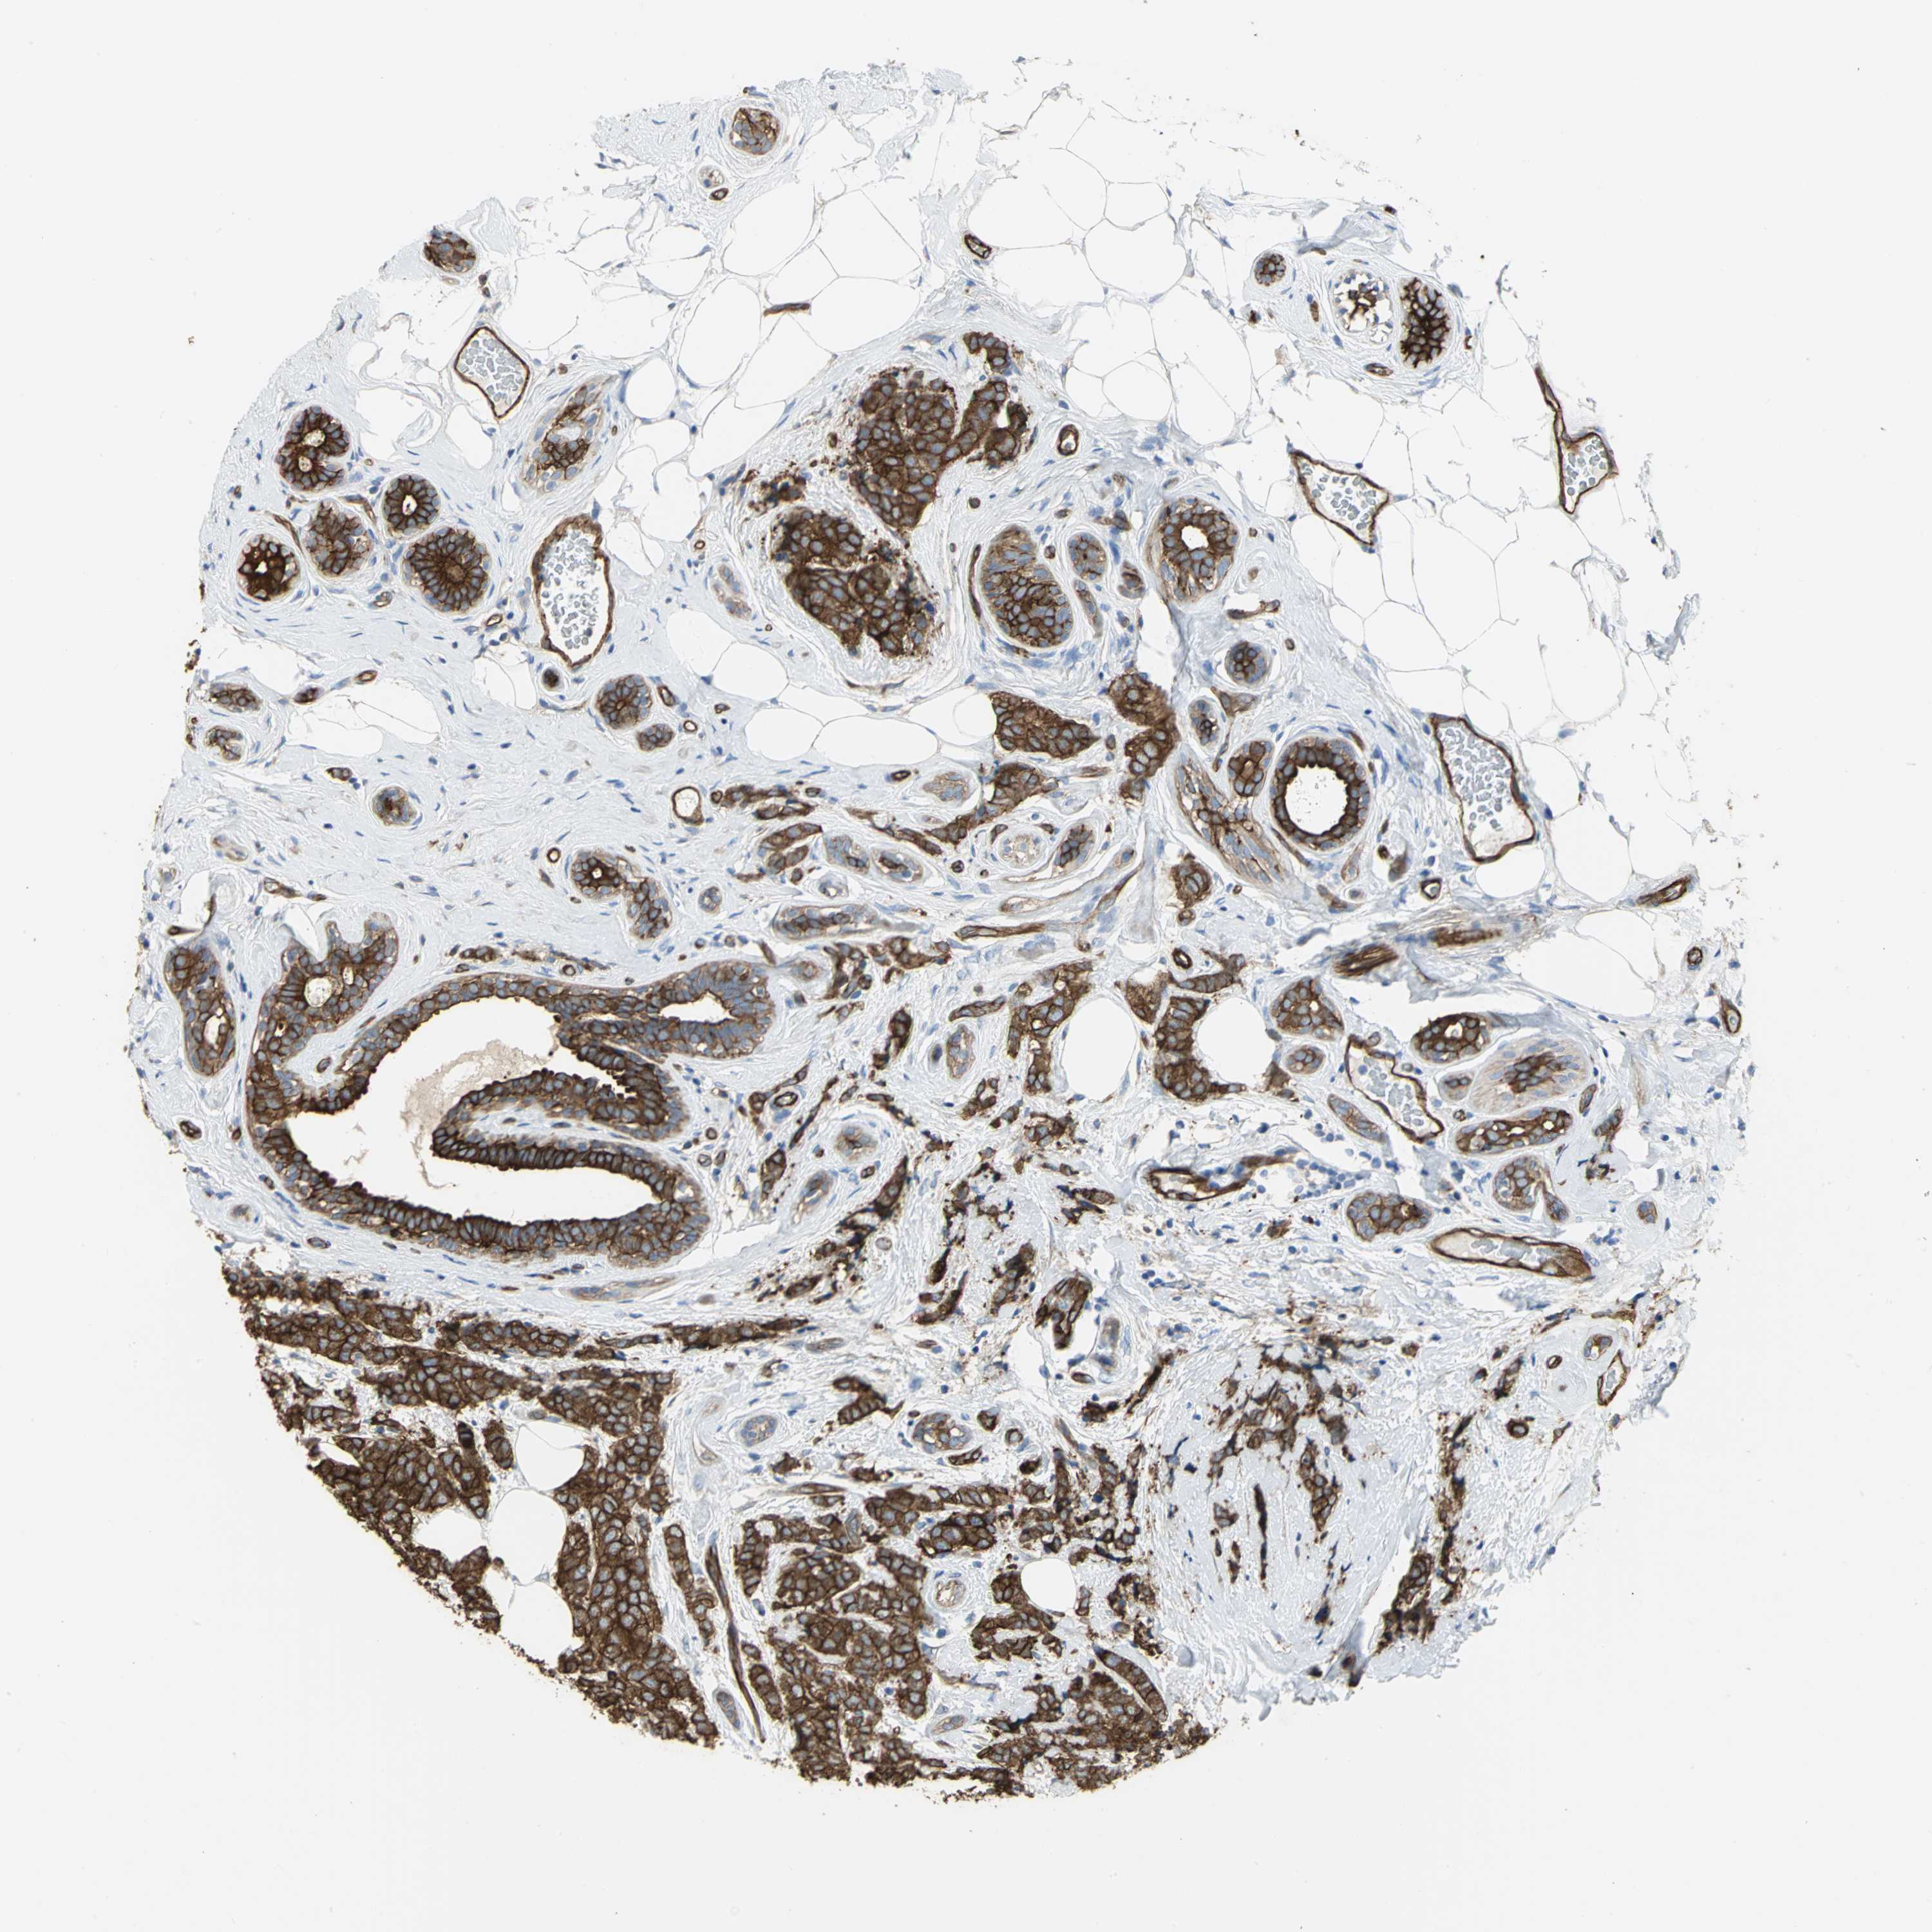

CANCER BREAST CANCER Show tissue menu

BRCA TCGA BRCA VALIDATION PROTEIN EXPRESSION

ANTIBODIES

AND

VALIDATION